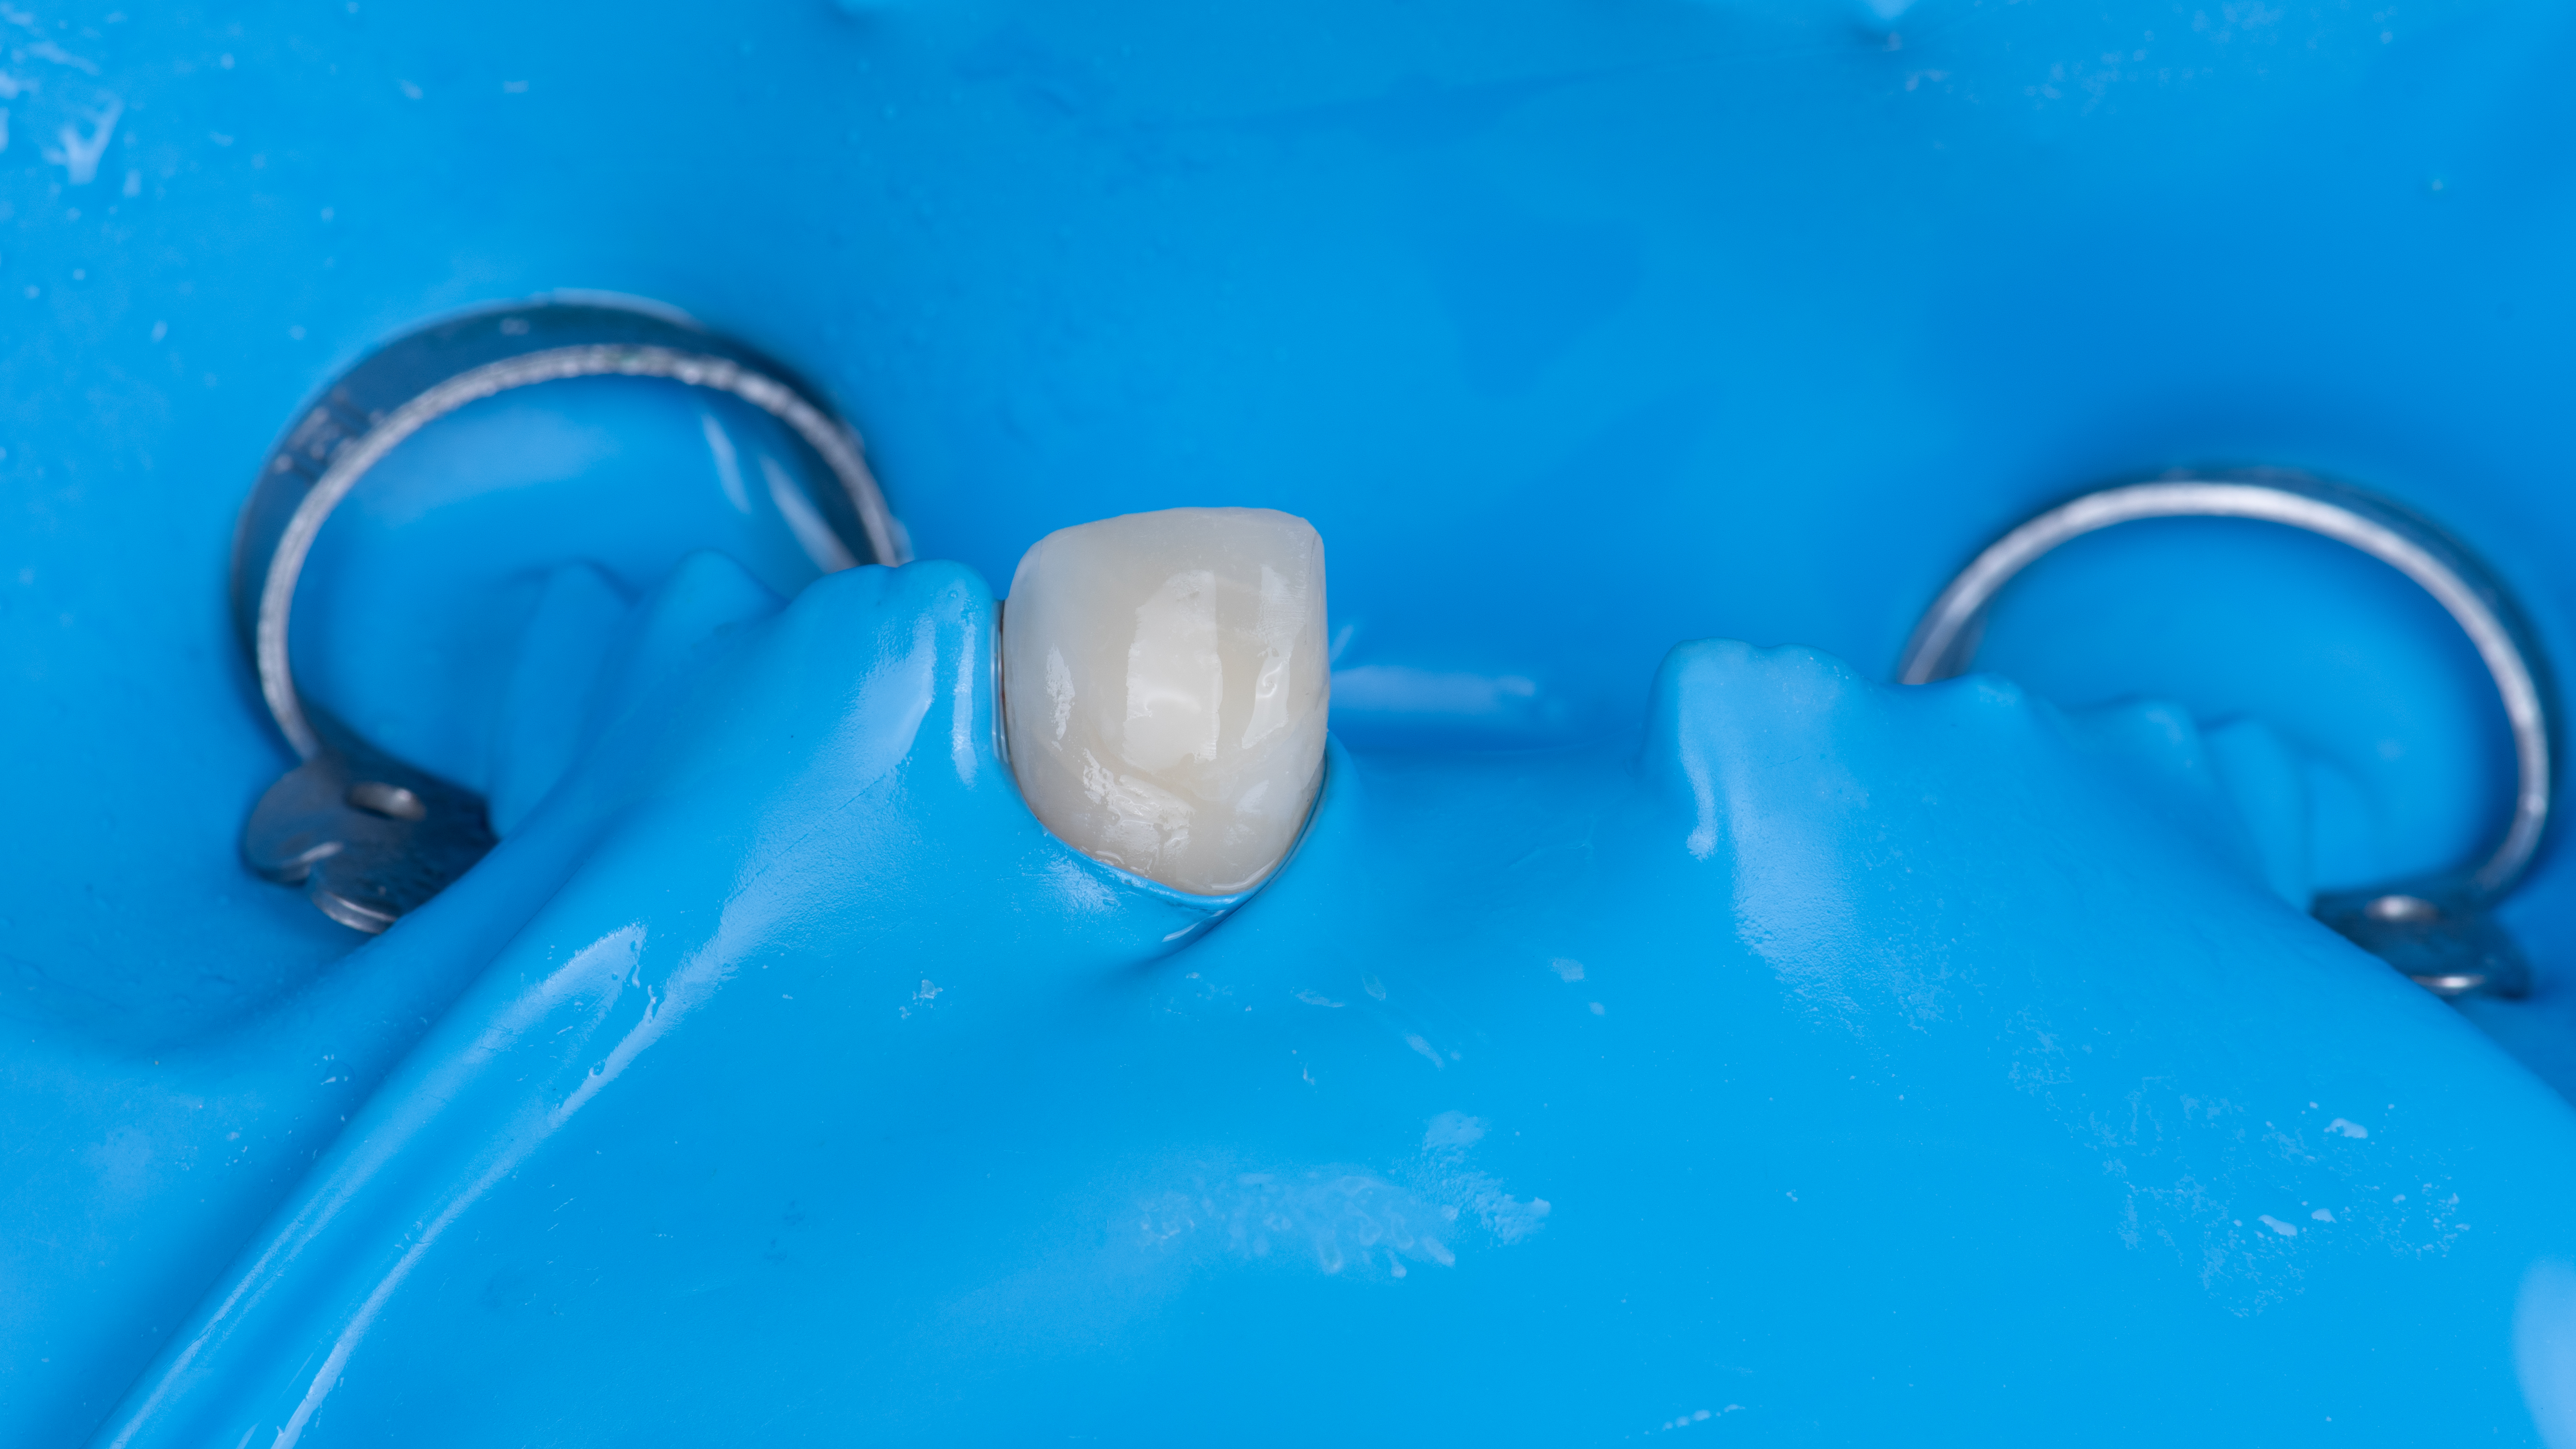

Une copie de la couronne de la patiente est imprimée et évidée pour permettre de la positionner correctement. Elle est ensuite solidarisée à un pilier provisoire vissé dans l’implant. Ceci nous permet ensuite d’ajuster le profil d’émergence (Photo 12).